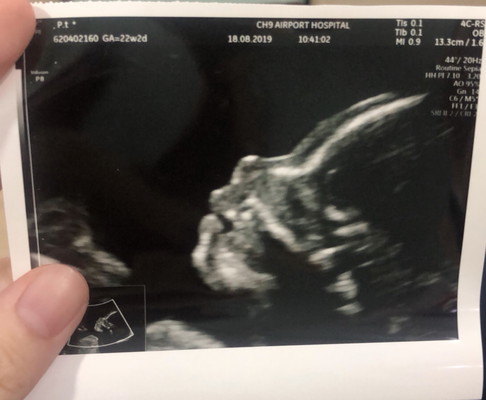

❤️ของแม่ # 23W2D